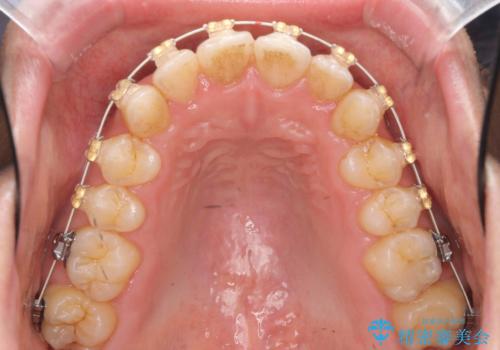

- 矯正装置

- 審美装置

- 1年6ヶ月

- 10-30回

- 前歯のガタガタを主訴に来院。

奥歯はすれ違ってしまっていました。

口元も出ておらず、非抜歯を希望されたため、IPR(歯を削る処置)でスペースを確保しました。

上顎両側7番(一番奥の歯)はすれ違っており、虫歯になっていました。